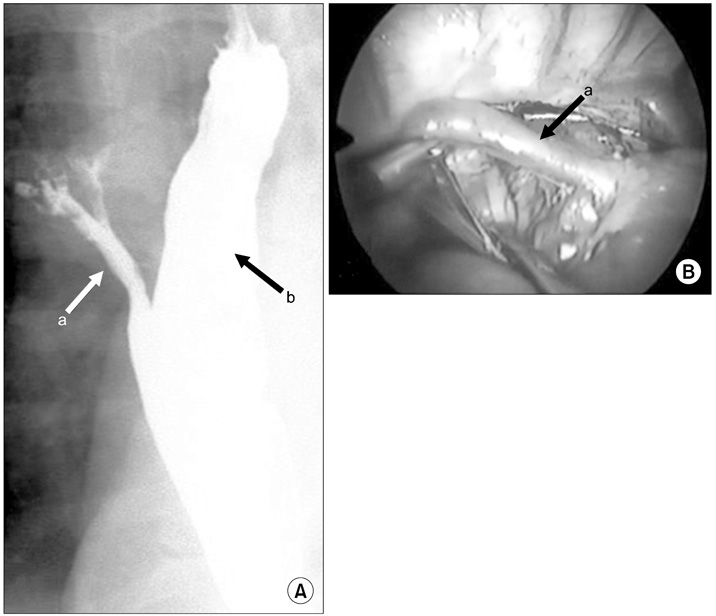

Esophageal bronchus. (A) Upper gastrointestinal series showed a community between esophagus and trachea. The contrast also showed that bronchus and bronchioles are risen from esophagus. (B) Intraoperative photo. There was fistula tract between bronchus and esophagus, so it was ligated with simple suture. Patient underwent thoracoscopic right upper lobectomy and fistula division. Arrows: a, fistula tract; b, esophagus.

Fig. 5 Esophageal bronchus. (A) Upper gastrointestinal series showed a community between esophagus and trachea. The contrast also showed that bronchus and bronchioles are risen from esophagus. (B) Intraoperative photo. There was fistula tract between bronchus and esophagus, so it was ligated with simple suture. Patient underwent thoracoscopic right upper lobectomy and fistula division. Arrows: a, fistula tract; b, esophagus.